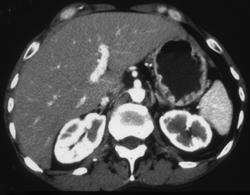

Pseudomyxoma Peritonei (PMP)